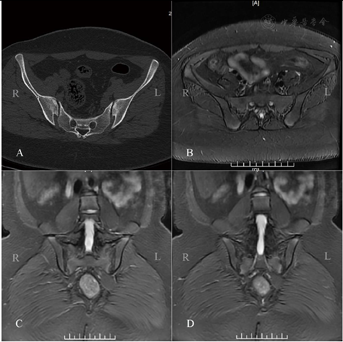

2022年7月4日脊柱全长X线片:双侧骶髂关节面部分显示欠清。2022年7月4日骶髂关节CT:双侧骶髂关节软骨下骨质稍毛糙,关节面密度稍增高(图1A)。2022年8月4日骶髂关节磁共振增强扫描:双侧骶髂关节软骨下骨质稍毛糙,关节面下可见斑片状稍长T1稍长T2信号影,增强扫描轻度强化(图1B~D)。

有文献总结了127例FM患者的临床特点,其中有71例患者合并有骶髂关节炎,其检出率大于50%,且其中21例患者符合欧洲脊柱关节病分类标准[6]。纤维肌痛症患者不排除其他器质性疾病[5],该患者初始腰背部及臀区疼痛合并影像学骶髂关节炎表现容易误诊为强直性脊柱炎,但患者HLA-B27阴性,且骶髂关节影像学表现不典型,CT未见关节面破坏、狭窄或融合,MRI无典型炎性改变,不符合强直性脊柱炎的骶髂关节表现,根据2009年ASAS中轴型脊柱关节炎(axial spondyloarthritis)分类标准[7]诊断为中轴型脊柱关节炎,需注意不可误诊。